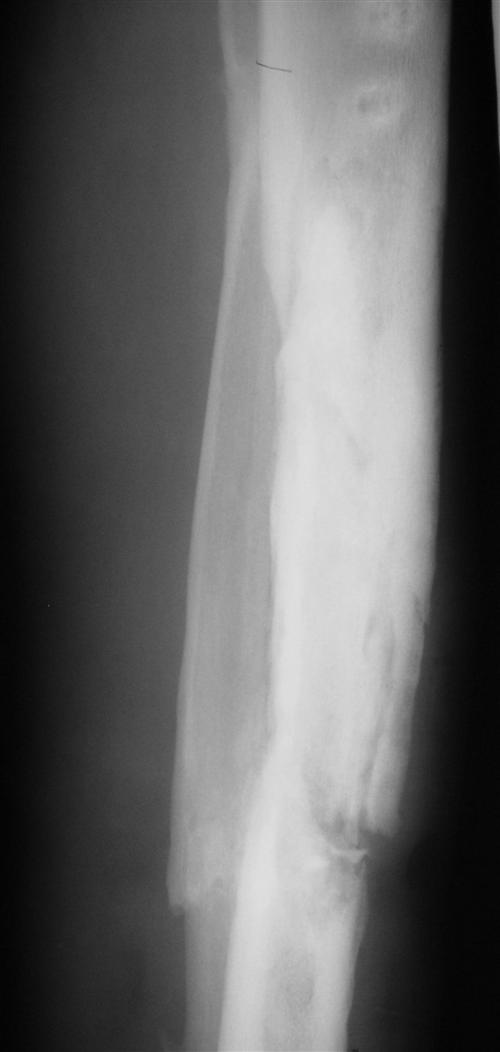

慢性化脓性骨髓炎是急性化脓性骨髓炎的延续,往往全身症状大多消失,只有在局部引流不畅时,才有全身症状表现,一般症状限于局部,往往顽固难治,甚至数年或十数年仍不能痊愈,下面我们来看看慢性骨髓炎饮食需要注意一些什么呢?

相关图片